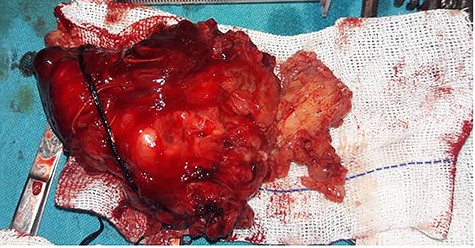

After obtaining the patient’s informed consent, surgery was planned to approach the deeper lobe of parotid gland and para-pharyngeal mass by transparotid, transmandibular swing approach in order to achieve radical excision of the mass. Superficial parotidectomy was done to preserve the facial nerve. After exposure of the parasymphysis, body and ramus of the mandible, mandibular swing access osteotomy was planned. The osteotomy cuts were planned by preserving the inferior alveolar neurovascular bundle, and the media surface of the mandible was exposed to visualize parapharyngeal structures. The facial nerve branches around the tumor were dissected out past the mass, so that the tumor could be peeled away from the facial nerve (Fig. 2). It was completely excised in toto. The measurements of the tumor were 16 × 10 × 4.5 cm in size (Fig. 3). Histopathological examination revealed the features suggestive of pleomorphic adenoma. The patient was discharged after 9 days with no facial nerve deficit.

Intraoperative image shows that facial nerve branches around the tumor were dissected out past the mass, so that the tumor could be peeled away from the facial nerve.